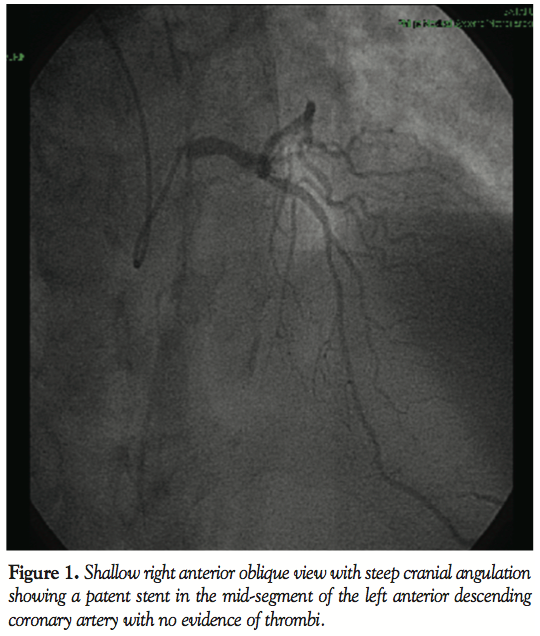

In January 2010, the patient discontinued clopidogrel. After 2 weeks, he experienced recurrent angina (Canadian Cardiovascular Society score II) and was admitted once again to our critical care unit. Nevertheless, electrocardiography was unremarkable, and cardiac biomarkers were within the normal range. In the context of multiple risk factors, the previously implanted stent, and more importantly, the recent discontinuation of clopidogrel, he was triaged for invasive study. Interestingly, coronary angiography revealed normal opacification of the index artery with no in-stent restenosis, and notably, no evidence of thrombosis (Figure 1). Obviously driven by a high index of suspicion, the operator decided to explore the artery with optical coherence tomography (OCT). Anticoagulation was achieved by enoxaparin 1 mg/kg intravenously (90 mg). Surprisingly, OCT (LightLab Imaging Inc.) discovered a ribbon-like thrombus starting in the proximal part of the stent and extending beyond its distal part. OCT was also able to clearly demonstrate a substantial proportion of uncovered and malapposed stent struts in the proximal part of the stent and a good deal of neointimal hyperplasia in its distal part (Figures 2A-2C). After a guidewire passage, thrombectomy was effectively performed using a thrombus-aspiration catheter, and a red thrombus was eventually extracted (Figure 3). Following thrombectomy, OCT confirmed adequate removal of the thrombus (Figure 2D). No balloon angioplasty was performed for stent malapposition because only a few malapposed struts were observed. Cardiac biomarkers were persistently negative at 6- and 12-hour intervals. The patient was kept on dual antiplatelet therapy in the form of aspirin 100 mg/d, and clopidogrel 75 mg/d for 12 months.